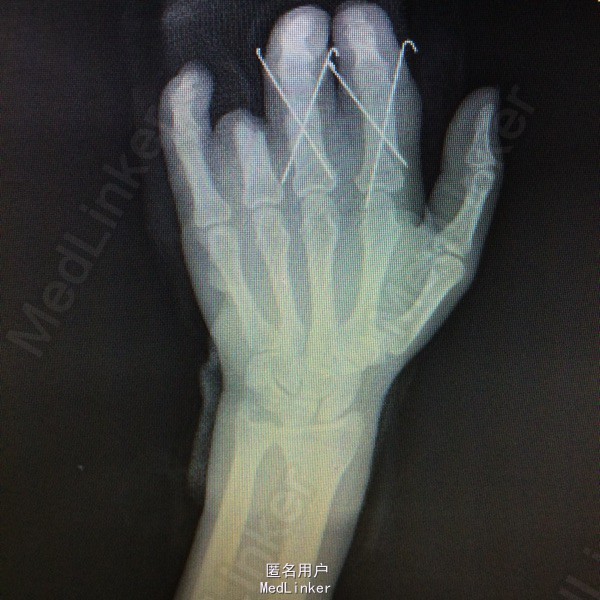

体格检查:T:36.3°,P:80bpm,BP:120/75mmHg,R:20bpm。神清皮肤巩膜无黄染,浅表淋巴结未及。头颅形状无畸形,口唇无紫绀,气管居中。双肺呼吸音清,未闻及干湿罗音。HR:80bpm,心律齐,各心脏听诊区未闻及明显病理性杂音。腹部平软,无压痛及反跳痛。生理反射存在,病理反射未引出。 专科检查:左手2-5指指根部环形伤口,伤口不规则,皮下组织部分分离,左手2-5指少许畸形,局部触痛明显,伤口以远灰色,无血供,感觉消失,关节屈伸活动受限。 辅助检查:2015-5-12日我院X片检查提示:左手及2、3、4近节指骨粉碎性骨折;左腕游离骨片影,考虑陈旧性外伤所致,请结合临床。(D00300044)。

初步诊断:左手2-5指压伤不全离断 治疗计划:1、完善相关检查及术前准备:心电图,血常规,尿常规,肝肾功能电解质、术前全套等。 2、臂丛麻醉下行再植术。 3、术后“三抗”治疗,烤灯保暖。再植术 左手2-4指骨折复位交叉克氏针固定,

左手2-4指骨折复位交叉克氏针固定,透视检查骨折复位固定良好;患者诉伤口轻度疼痛,无发热症状。查体:伤口无异常分泌物,手指血供良好,手指屈伸受限。主任医师查房查房看过病人,患者术后第10天,拟明日出院,嘱定期伤口换药,门诊随诊。 请问各位专家,术后多久康复锻炼效果最好,?怎么预防坏死?